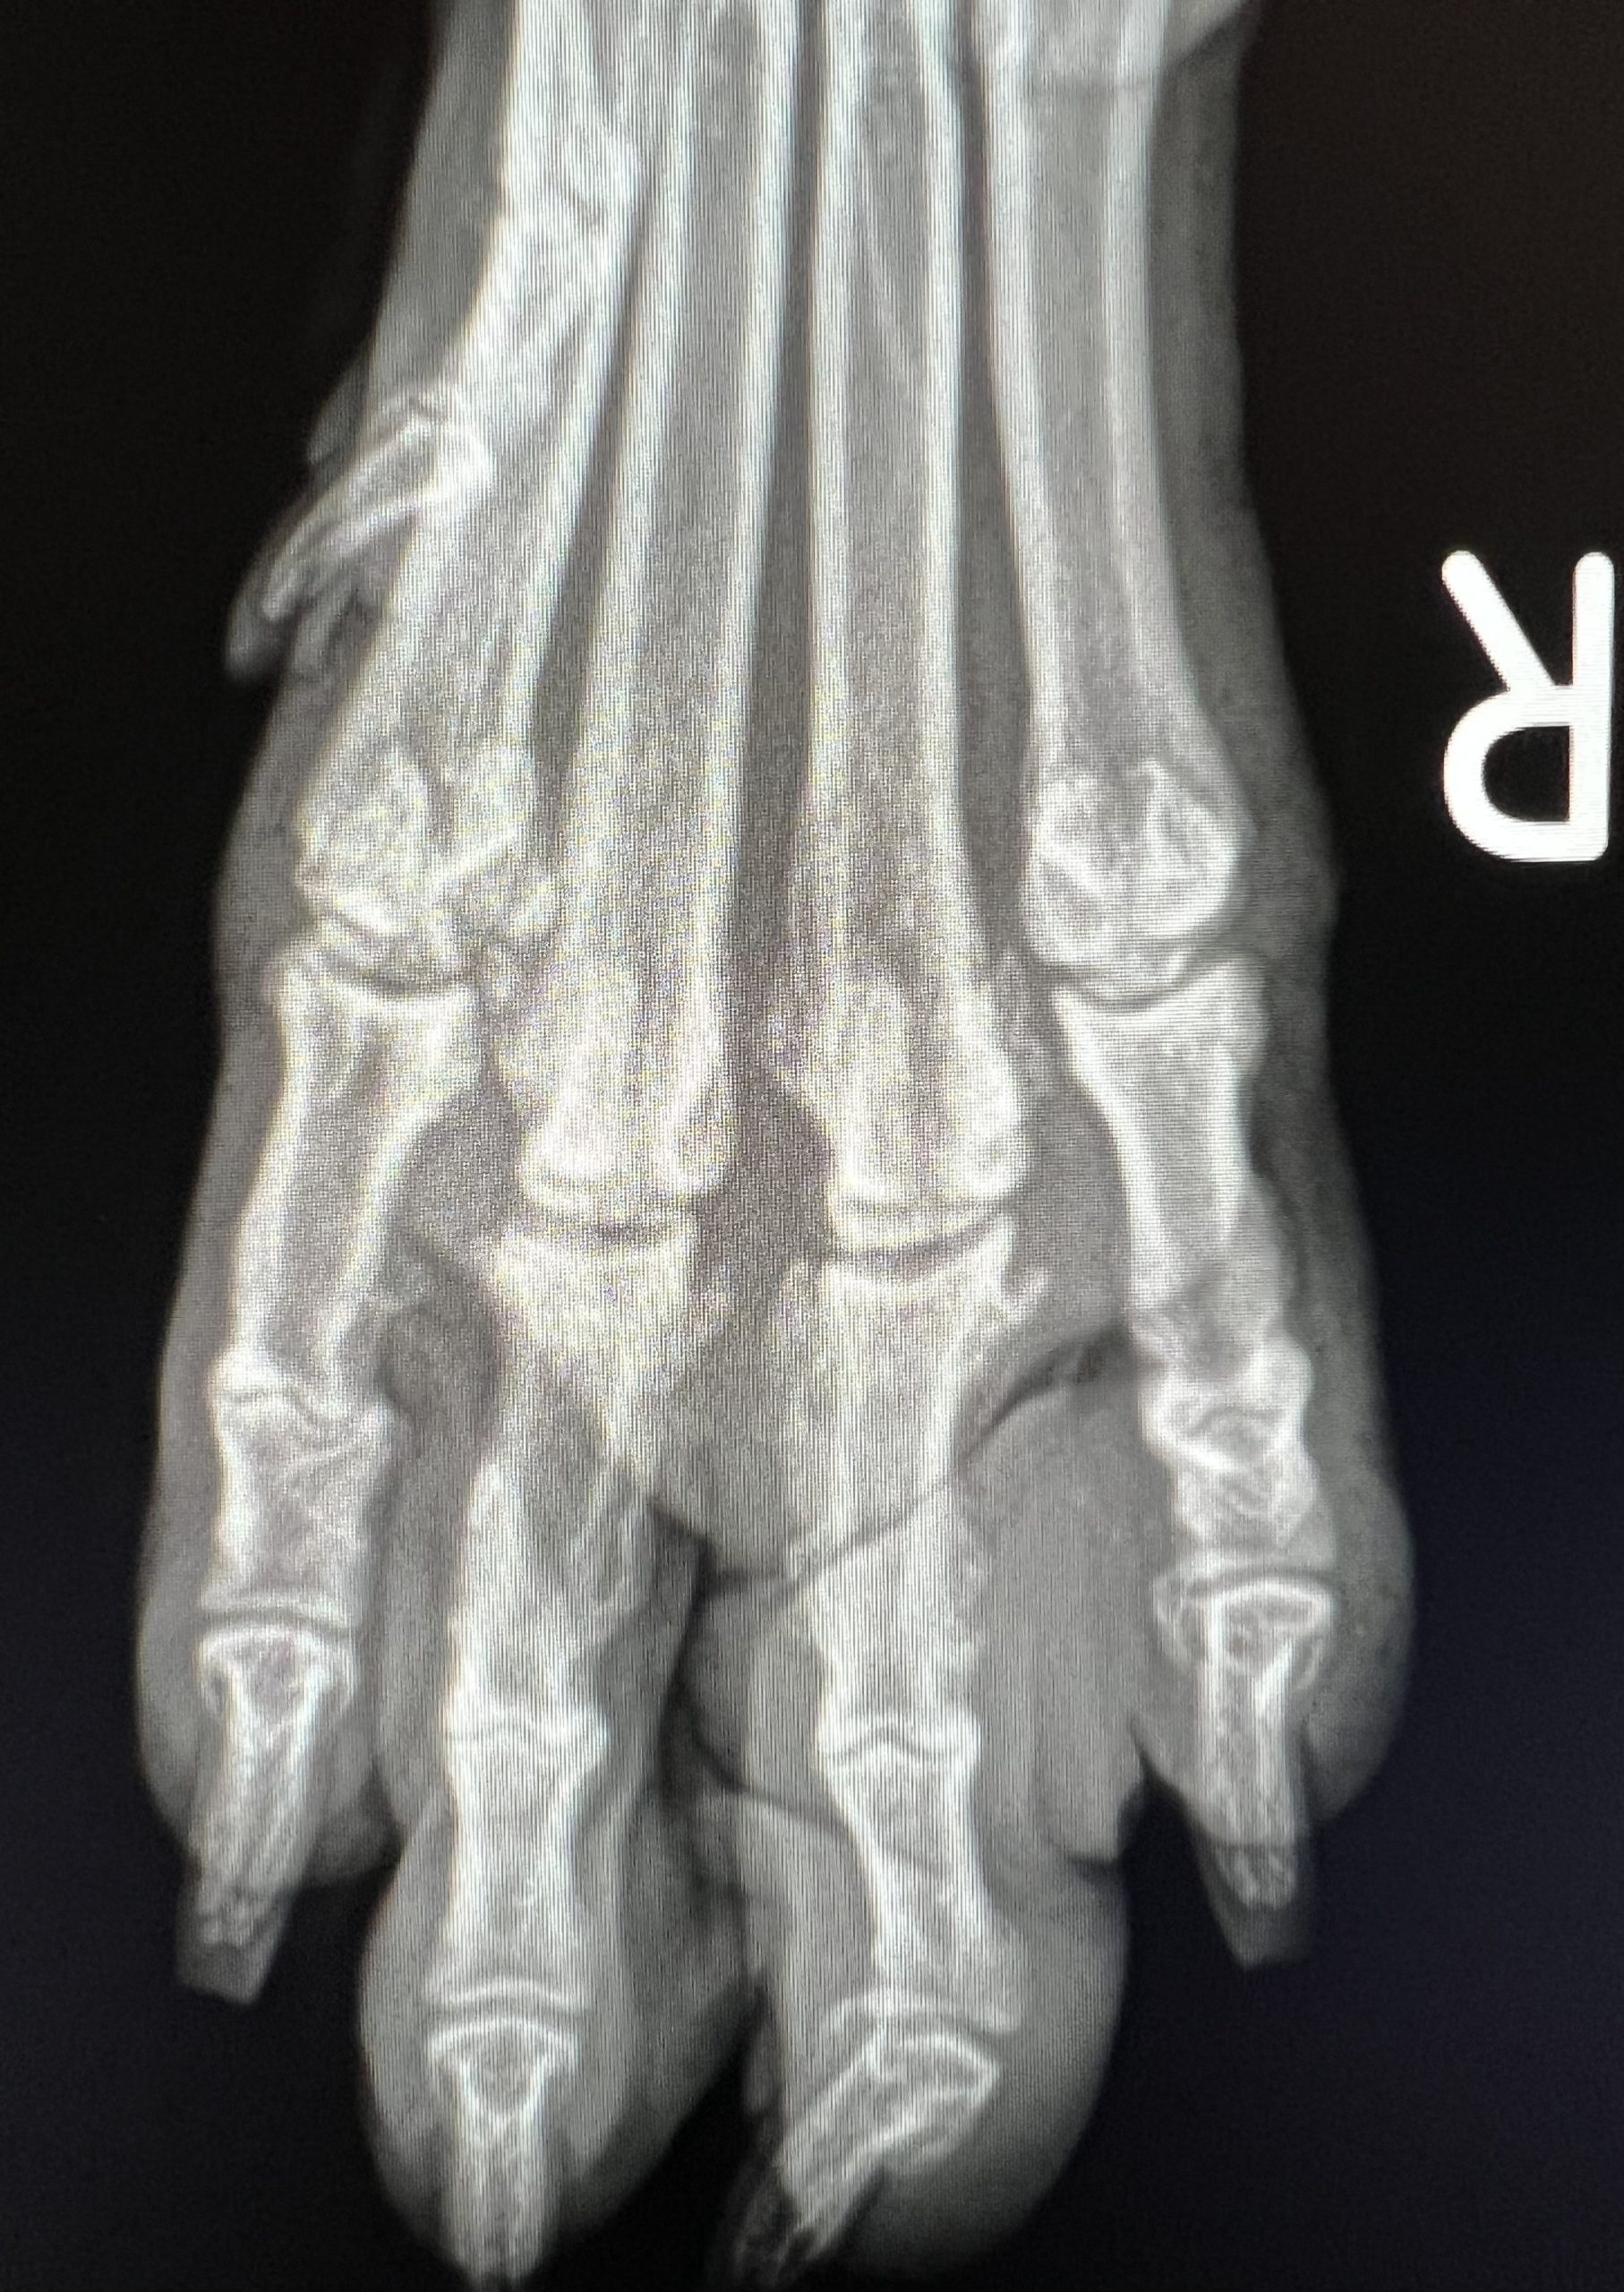

Artros kan drabba både  hundar och katter. Symtomen på hund är vanligen hälta, stelhet eller svårigheter att hoppa in i bilen eller upp i favoritsoffan. Katter med artros kan visa lite andra typer av symtom som att de plötsligt kissar eller bajsar utanför lådan på grund av smärta när de ska kröka rygg. Vid undersökning  av ditt djur försöker man lokalisera var smärtan sitter och oftast röntgas djuret. Artros och/eller ledsmärta eller muskelinflammation kan behandlas på många olika sätt beroende på vad orsaken är och vad som ger bäst lindring i de olika fallen. Oftast är det en kombination av  smärtlindrande och antiinflammatoriska läkemedel i  kombination med rehabilitering.